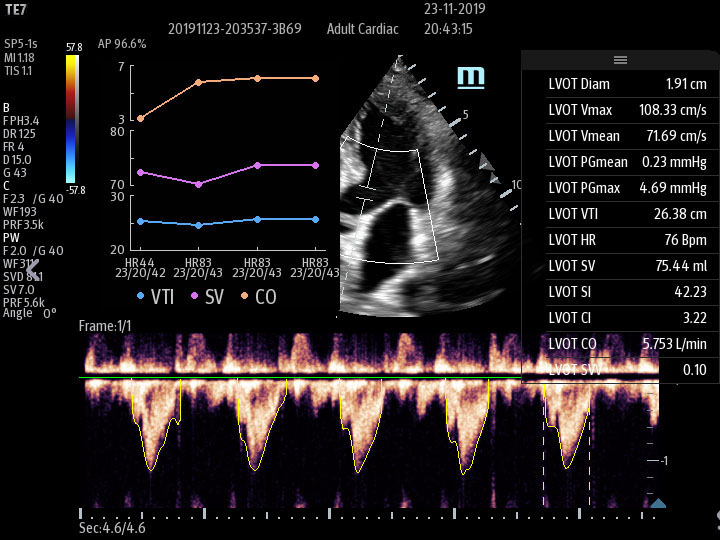

Smart VTI

Automated measurement of the Velocity Time Integral (VTI) and Cardiac Output (CO), enables rapid assessment of cardiac function. This software automatically locates color box and Pulse Wave Doppler (PW) sample line in real time. A graph of parameter trends for CO, Stroke Volume (SV) and VTI is produced to guide decision-making.